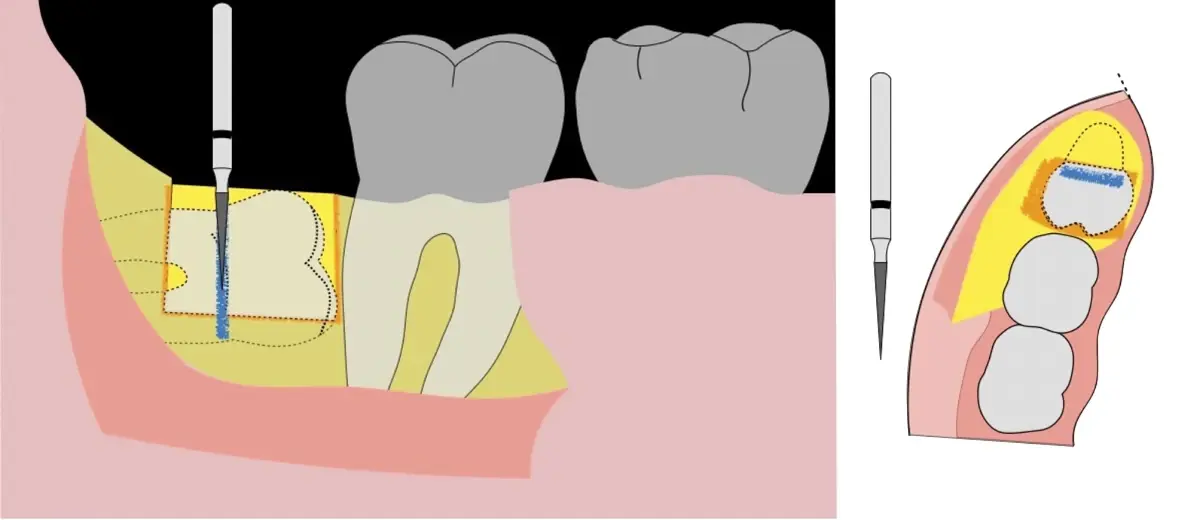

Figura 5. Fractura y eliminación oclusal del fragmento óseo de la porción coronal oclusal.

Figura 6. Demarcación y fractura de la zona de osteotomía a nivel vestibular con inserto aserrado recto y/o angulado.

Figura 7. Eliminación del fragmento vestibular.

Figura 8. Odontosección mediante fresa de alta rotación y/o inserto de corte de piezoeléctrico. Posteriormente se procede al ensanchamiento del espacio pericoronario con el periótomo de piezoeléctrico para facilitar la avulsión de la pieza dentaria.